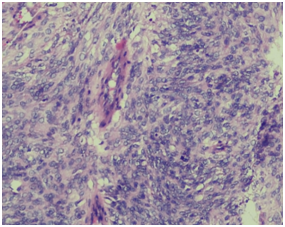

A 60 years old smoker, normotensive, non‒diabetic presented with chief complaints of cough, fever and weight loss for 20 days. On examination the patient was conscious, co‒operative, well oriented, with a respiratory rate of 18/min, blood pressure of 120/70 and pulse rate of 86/min. Cardiovascular and per‒abdomen examination were clinically normal. However, on auscultation decreased breath sounds were found on left lower side of chest. Chest radiograph revealed a lesion in the left lung. CT scan (contrast enhanced) of chest was done which showed a 71x59mm cystic lesion in the superior segment of left lower lobe. Cyst showed internal septations without calcification. USG abdomen and PFT (pulmonary function tests) were normal. Hydrated serology was negative and not suggestive. Routine complete blood counts, LFT (liver function test) and KFT (kidney function tests), were within normal limits. The patient underwent left postero‒lateral thoracotomy with lower lobe lobectomy. Intra‒operatively there was large bronchogenic mass occupying almost whole of the left lobe with multiple hilar nodes. On gross examination, we received a lobe of lung measuring 15x9.5x5cm. Serial slicing of the lung showed a well circumscribed mass measuring 7x8cm. Cut section showed variegated appearance with extensive hemorrhagic and necrotic areas. On light microscopy a spindle cell tumour was seen with cells having moderate to severe pleomorphism and mitosis of >10/10hpf, and extensive areas of necrosis (Figure 1a) (Figure 1b).

Figure 1b Higher magnification showing highly pleomorphic tumour cells (epitheloid type) arranged vessel with few mitotic figures.